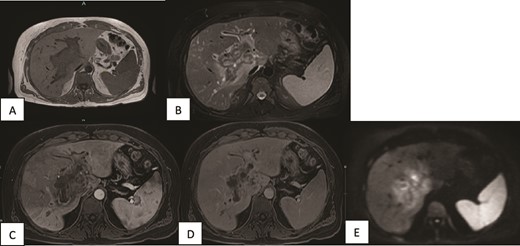

A contrast-enhanced CT scan of the abdomen and pelvis was done and revealed a dilated non-opacified main portal vein and superior mesenteric vein suggestive of thrombosis with periportal vascular congestion as well as a hypo-vascular geographic area with complex fluid density at the hilum of the liver and gallbladder fossa with dilated right and left hepatic biliary ducts. It also showed mild splenomegaly, colonic diverticulosis, and mild ascites mainly in the right iliac fossa. The splenic vein appeared normal, and there were no imaging features of bowel ischemia (Fig. 1).

Contrast-enhanced CT scan of the abdomen and pelvis in (A) axial and (B, C) coronal sections obtained at the porto-venous phase showing a hypo-vascular geographic area with complex fluid density at the hilum of the liver with intrahepatic biliary dilatation. Non-opacification of the main portal vein with early cavernous transformation was noted as well as mild splenomegaly and ascites.